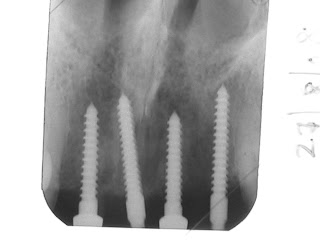

I placed in 4 minis.......yeah...just 4 minis and placed in a PFM bridge, all within a month in 2 visits. And I charged him a third what I would have charged him if I placed him conventionals.

The last picture was taken recently at age 82. Yeah, I did gain more than the patient's best interest.

Here are some more cases. For the atrophic maxillary anterior ridge, minimized dental implants should be the treatment of choice !!